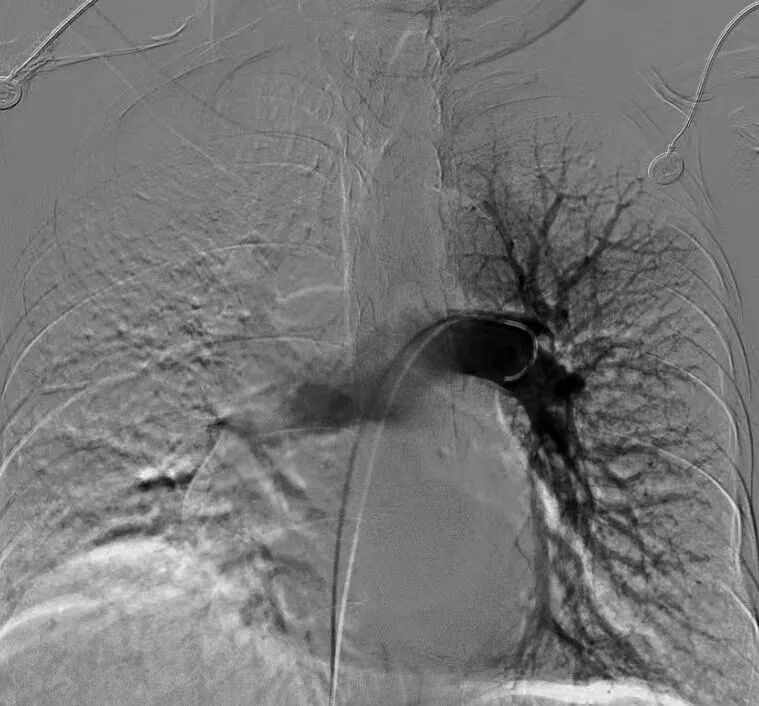

专家团队将Tendvia®血栓抽吸导管,沿导丝推送至左侧肺动脉,管口贴近血栓处停止,撤出导管芯。并将Tendvia®肺动脉取栓支架沿导丝通过抽吸导管向前推送,精确导入到患者的左侧肺动脉血栓部位。

再回撤输送鞘管,支架自动膨开,等待90秒,连接抽吸器并形成负压,回撤取栓支架的同时旋转开关释放负压,最后,Tendvia®肺动脉取栓支架捕获和收集血栓进入抽吸导管,经负压抽吸同步的作用下,顺利为患者取出左侧肺动脉血栓。

经过1个多小时的奋战,复查造影提示:左肺动脉干充盈缺损较前明显减少,血流通畅。患者胸闷症状立即得到缓解,血氧饱和度迅速回升,成功取出大部份血栓。